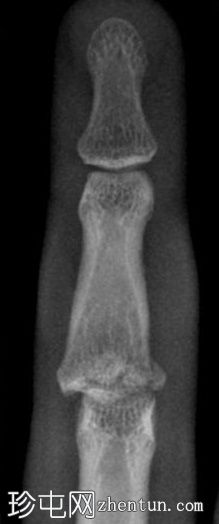

可见第三指中节指骨基底部轻微移位骨折,延伸至近端指间关节(PIP关节),并伴有软组织肿胀。

第三指中节指骨基底部轻微移位骨折,延伸至近端指间关节(PIP关节)指骨,并伴有软组织肿胀。